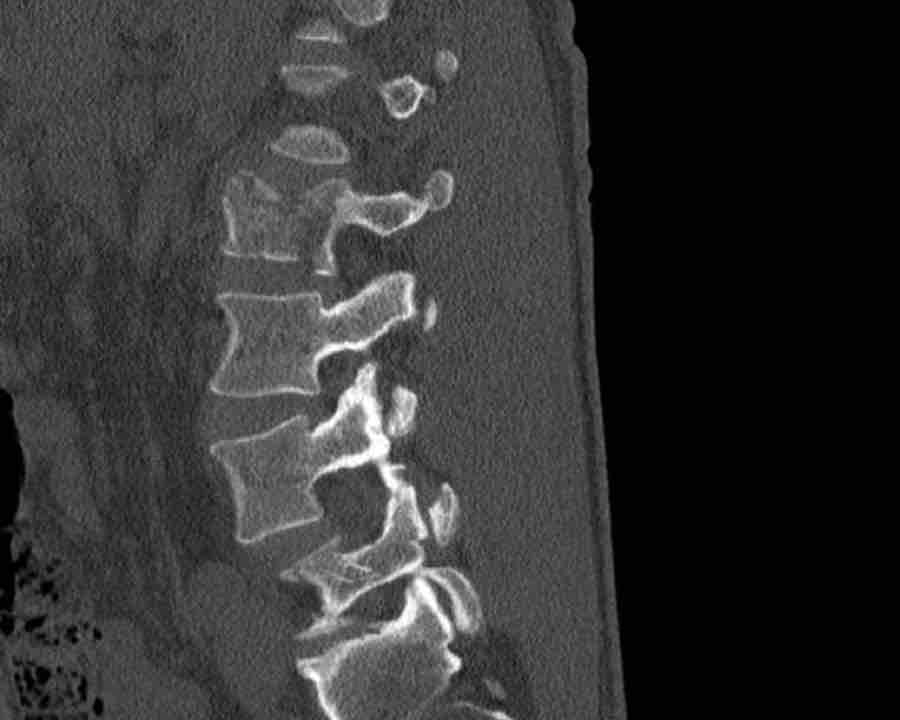

What is the highest AO-type of injury?

Findings

- No C or B injury.

- Fractures of the vertebral body with involvement of both endplates (1+1 points) and posterior wall (2 points).

- In the coronal plane, a sagittal course of the fracture is seen, which is common in burst fractures.

- Bulging of the posterior wall without any other signs of dislocation is the result of the burst fracture.

Therefore no C injury.

Conclusion

Injury type A4